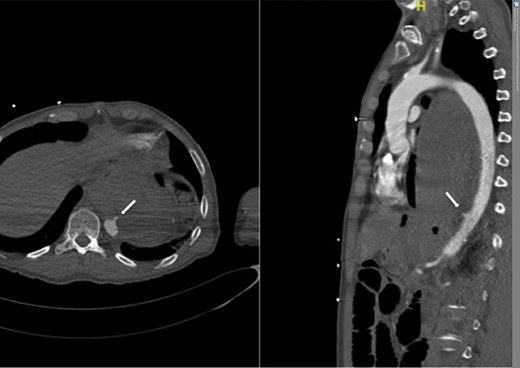

However, 4 and a half months later he again became haemodynamically unstable with a further episode of haematemesis. A further CT angiogram showed contrast entering the neo-oesophagus from the thoracic aorta (Fig. 5). The patient was again taken to the emergency theatre and the previous stent was relined with further stents extending both proximally and distally beyond the previous stent, with care taken not to occlude the celiac trunk and arteries below this (Cook Medical ZTA-26-105 and Cook Medical ZTA-28-109). Again, the patient had a quick recovery. However, repeat endoscopy showed that the aortic stent was visible through a defect in the wall of the neo-oesophagus (Fig. 6).

Second admission: CT angiogram showing aorta-enteric fistula demonstrated by arrow (axial and sagittal view, respectively).